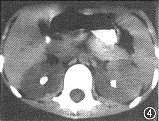

11例白血病肾浸润患儿中,9例为双肾浸润,其中双肾弥漫浸润4例,双肾多发结节浸润5例,9例中ALL 8例,ANLL 1例。CT平扫见弥漫浸润为两肾轮廓增大,肾包膜完整光滑,肾实质明显增厚,肾实质密度无异常,肾窦形态基本正常,增强后肾盂、肾盏显影轻度延迟。B超显示肾影增大、肾实质增厚的同时还显示回声均匀增强。 多发结节浸润的平扫CT见肾实质内多发的略高密度结节影,结节间可见线状低密度影将其分开(图1),结节突起使肾表面呈轻度分叶状。增强后肾实质内结节呈轻微强化,较平扫增长18 HU,密度均匀,结节内无低密度坏死区或出血,结节间见强化后受结节挤压变形的肾实质与集合系统,呈高密度分支状影(图2),肾实质强化程度较正常减低,在结节间自肾被膜下延伸至肾窦,肾盏变形拉长,肾盂显影明显延迟。B超显示肾实质回声增强,内见多发大小不等的结节(图3),中等强度回声,肾结构不清。化疗后复查,CT平扫显示双肾大小、形态基本恢复正常。本组2例呈单发结节浸润,均为ANLL。平扫CT见肾实质局限增厚,表面隆起,密度较正常肾实质略高,境界模糊(图4),增强后见肾实质内单发结节状影轻微强化,较平扫增长22HU,结节与正常肾实质间界限清楚(图5),肾被膜完整。B超显示肾实质内孤立中等强度回声结节(图6),肾结构受挤压变形。化疗后复查B超显示肾形态基本恢复正常。 本组化疗后5例复查CT与B超,显示肾轮廓明显缩小,肾实质厚度、密度或回声接近正常。11例患儿肝、脾均有不同程度增大。8例ALL患儿CT或B超检查同时显示胸腺浸润1例;肺及胸膜浸润4例;肾上腺浸润2例;腹膜后淋巴结浸润1例。3例ANLL患儿除肝、脾增大外CT或B超检查未显示其他脏器浸润。

图4 女,8岁。急性非淋巴细胞白血病。单发结节肾浸润。平扫显示左肾实质局限增厚,密度较正常肾实质略高,边界模糊